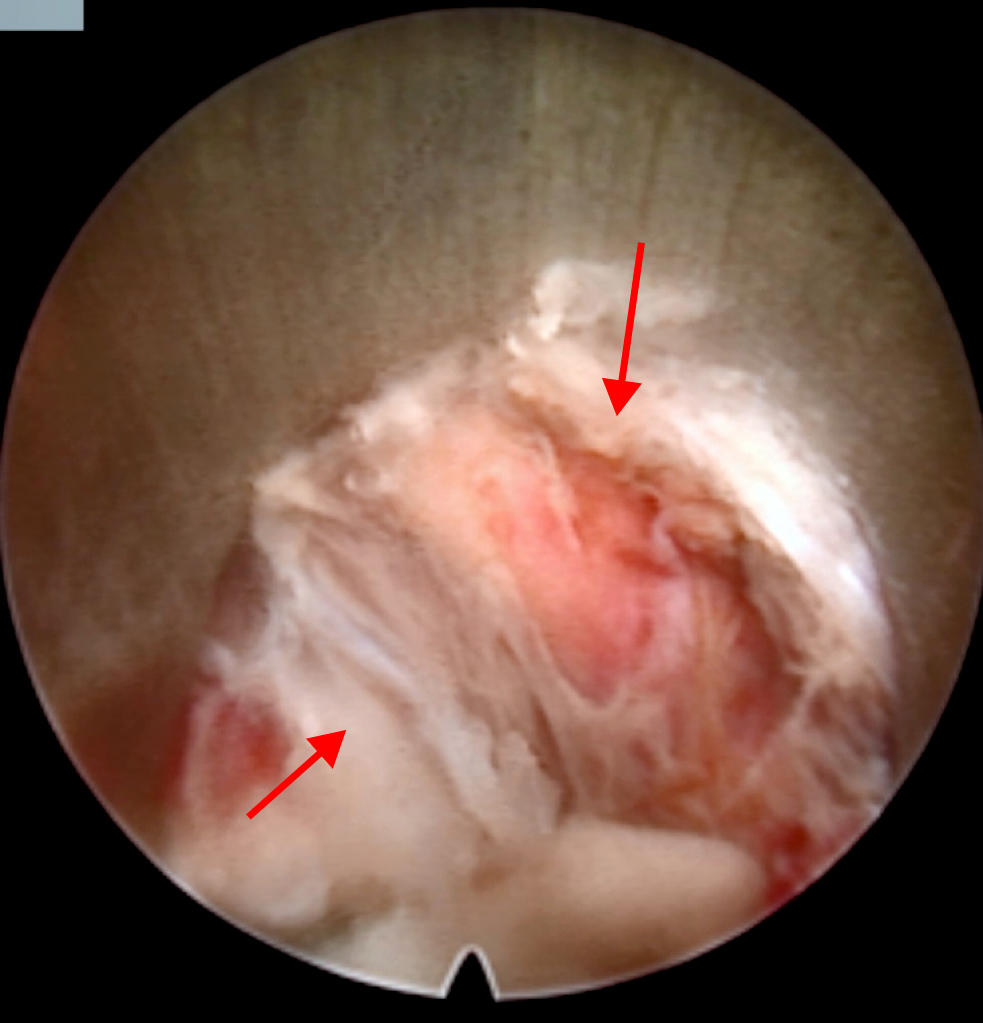

图4(1)出口根及突出椎间盘

DM_20240523090618_007.PNG

图4(2)减压后出口根

术中需要特别注意椎弓和横突的定位,这有助于确定突出的具体位置,避免误操作,此外清晰显露硬膜和出口根是术中确保神经损伤的核心。通过精准剥离和显露,可以避免对神经根的损伤,提高手术的安全性和效果。